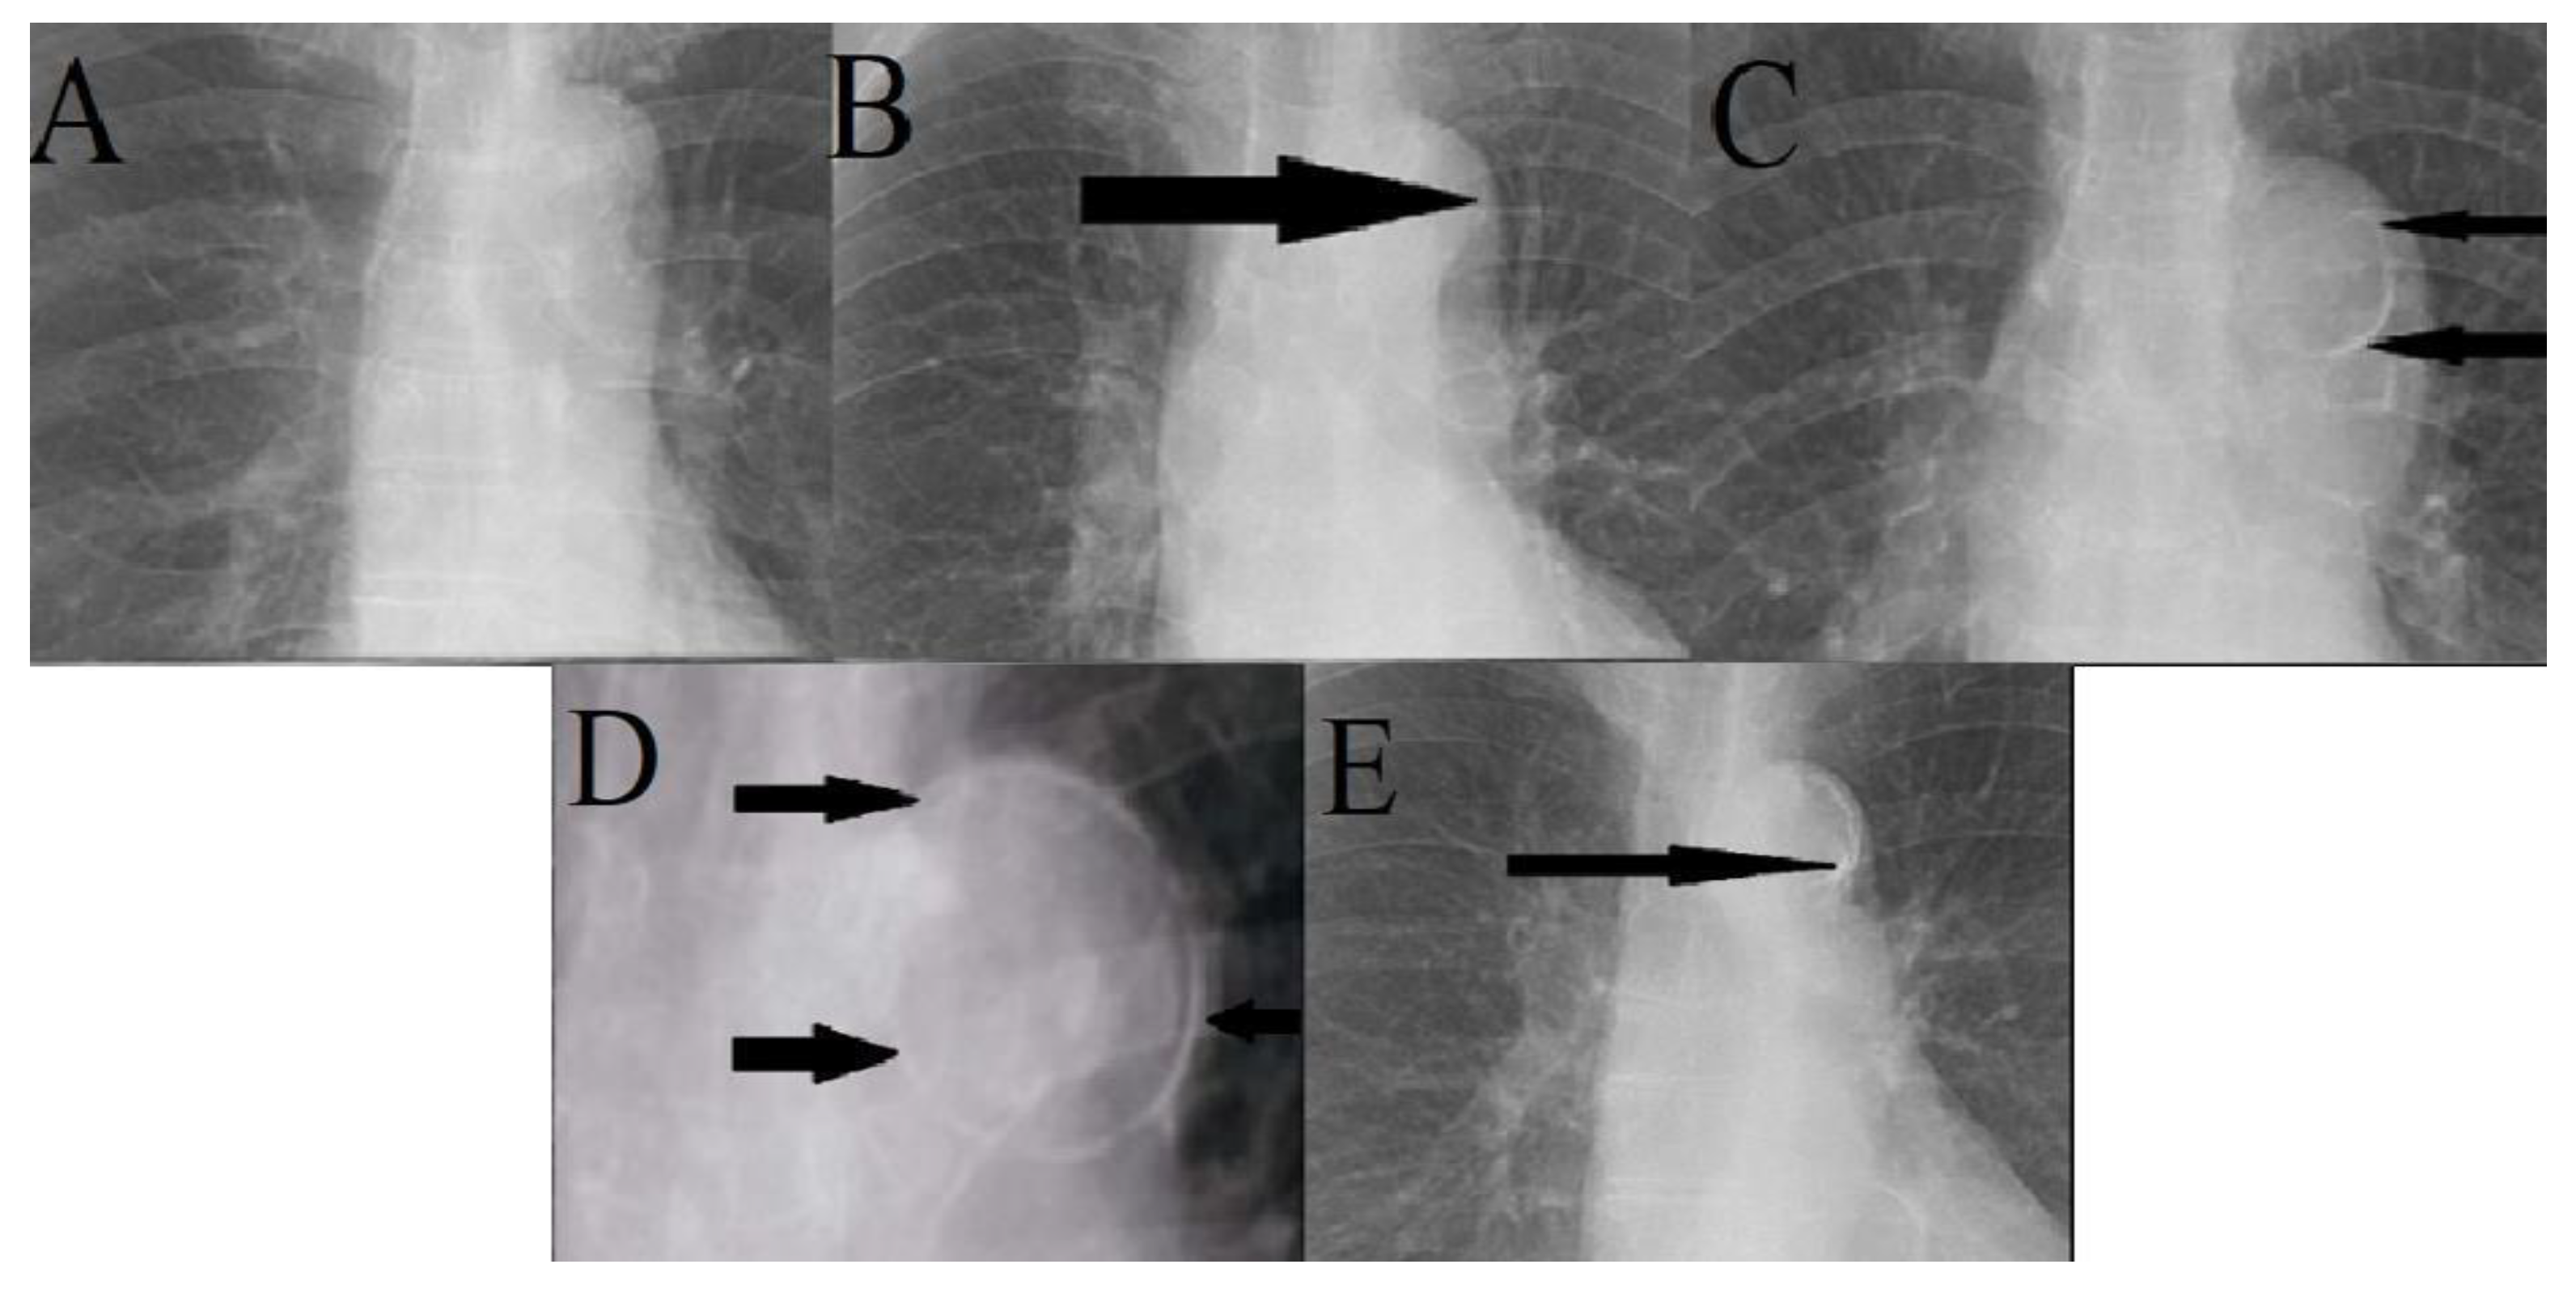

Chest Radiographs Grading Of Aortic Arch Calcification Five Frontal Download Scientific Diagram